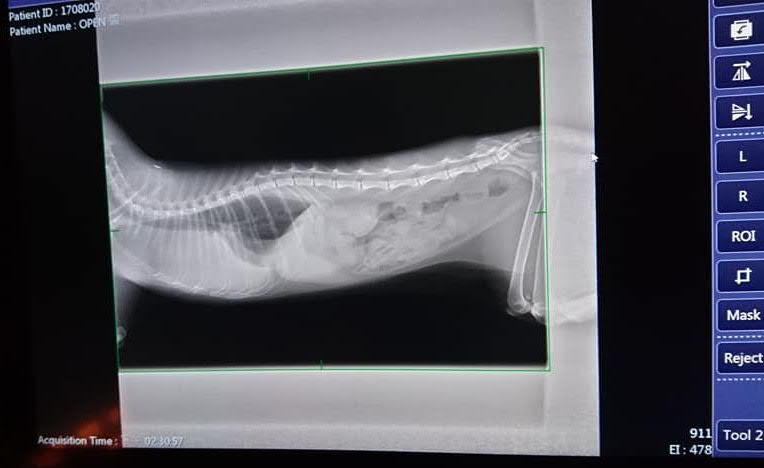

上回4.215kg 今日回診3.76kg瘦很多,發燒40℃有輕微脫水,暫時不打水怕打的水跑到胸肺去,牙齦很紅,後口部份沒有到紅腫,今日血檢白血球比較高,照X光後發現有胸水,需抽胸水檢驗,今日左胸抽出108ml 右胸抽出66ml 量很多,原本含氧值84∼85%抽完胸水到99%正常值,表示可以正常呼吸

血檢結果,白蛋白和總蛋白比值很低,類似冠狀傳染性腹膜炎,會將檢體送至PCR診斷,可能是某種狀況而引發病毒變異,現進行支持療法,但要等PCR和細菌培養結果後才能確診。